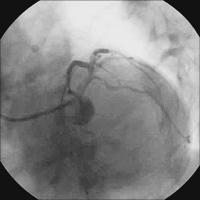

Vordilatation LAD

Abbildung 4: Vordilatation LAD mit 2,5/20-mm-Ballon - 16 atm.

Keywords: KardiologieKoronarangiographieVordilatation